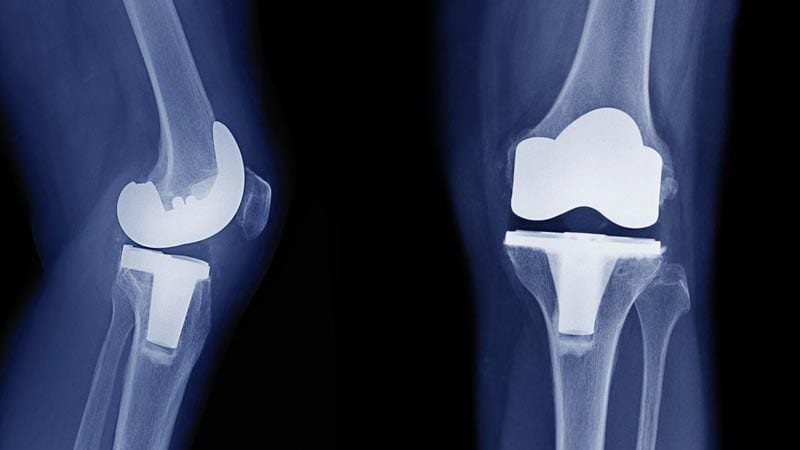

Обикновено ставните повърхности са покрити с хлъзгава и гладка хрущялна тъкан. По този начин движенията са плавни и безболезнени. Износването на повърхностния хрущял на ставата увеличава триенето при движение и ставните движения стават ограничени и болезнени. Подмяната на увредените повърхности на ставата се нарича протезиране на ставата (поставяне на изкуствена става).

Разработени са различни хирургични методи при ендопротезирането на тазобедрената става, като използваните изкуствени протези могат да бъдат от метал, керамика или полиетилен за удължаване на издръжливостта и живота на използваната изкуствена протеза. Кой хирургичен метод и какъв вид протеза ще бъде използвана при конкретния пациент зависи от фактори, като възрастта на пациента, общото здравословно състояние и тежестта на проблема с тазобедрената става и професионалната квалификация и опита на на хирурга- ортопед.

Основните видове протези са безциментни и циментирани, като и двата вида фиксиране на протезите са широко използвани в медицинската практика. В някои случаи хирургът може да използва комбинация и гнездото на ставата да се фиксира с цимент, а бедрения компонент е безциментен. Ортопеда-хирург преценява дали да използва циментирана или безциментна протеза, според възрастта, начина на живот и качеството на костите на пациента.